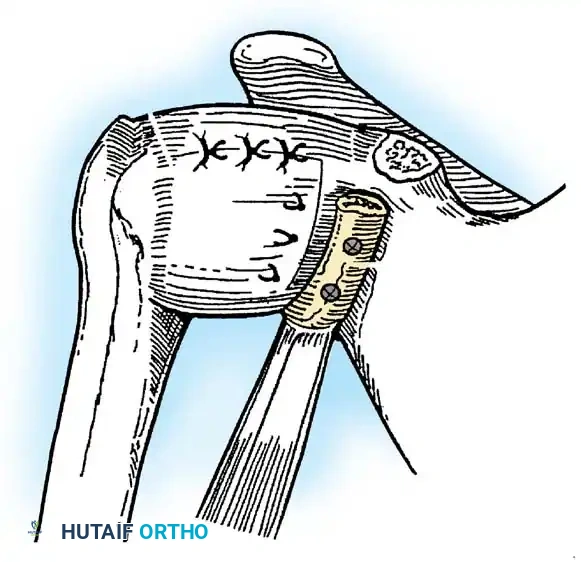

Capsular Shift and Closure

To address capsular redundancy, an inferior capsular shift is performed.

- The arm is positioned in 30 to 45 degrees of abduction and 20 degrees of external rotation.

- The inferior capsular flap is advanced superiorly and laterally, tensioning the IGHL complex. The sutures from the anchors are passed through the shifted capsule and tied.

- The superior flap is then brought down over the inferior flap in a "pants-over-vest" fashion to reinforce the anterior wall and close the rotator interval.

- The subscapularis split is loosely approximated with absorbable sutures. The deltopectoral interval is closed over a suction drain (if necessary), followed by routine subcutaneous and skin closure.